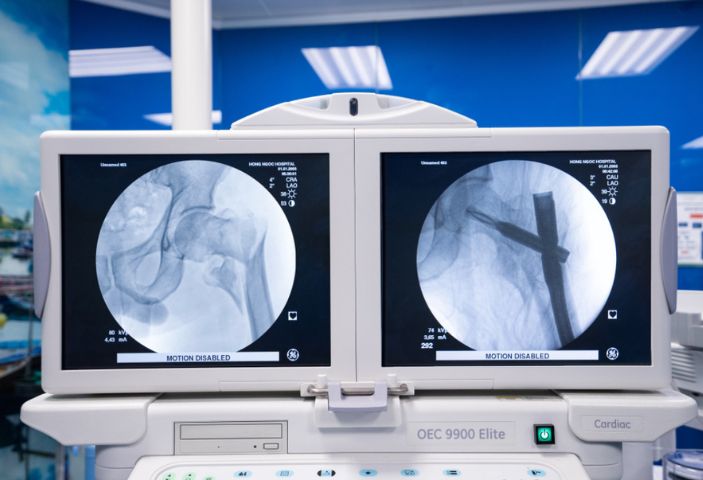

최첨단 장비: 정형외과 수술대, C-arm 장비 및 첨단 수술 지원 시스템을 갖추고 있습니다. 이러한 장비는 골절 부위를 정확하게 파악하고, 뼈를 올바른 축으로 정렬하여 수술 후 합병증을 최소화합니다.